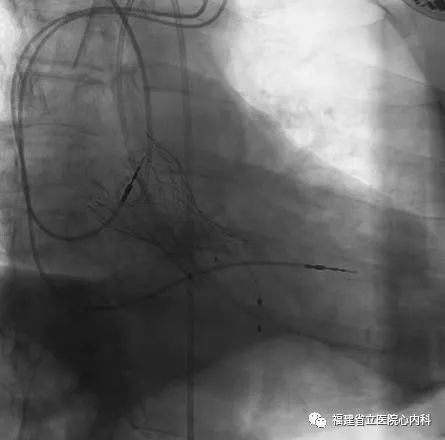

病例5

该病例是功能性二叶瓣,瓣叶增厚,重度钙化,左无钙化融合,形成明显瓣上限制结构,同时合并横位心,对于瓣膜的定位及锚定增加了一定难度,手术过程术者们精细操作,稳定释放,最终26号瓣膜精准定位,成功解除患者的狭窄问题,术后患者症状改善明显。

瓣环

窦部

球囊预扩张

植入L26瓣膜